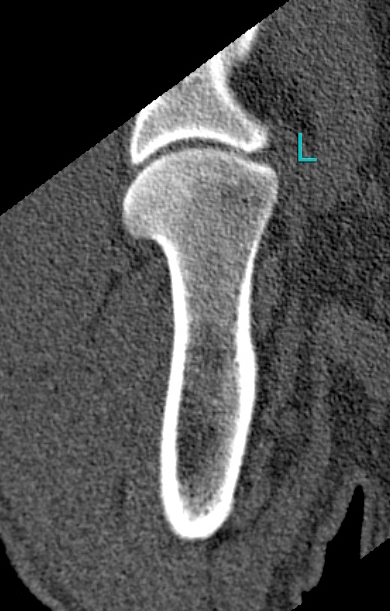

- This is also left. Mind, that the leg he limps with but that looks the best on both the x-rays as the ct-scan.